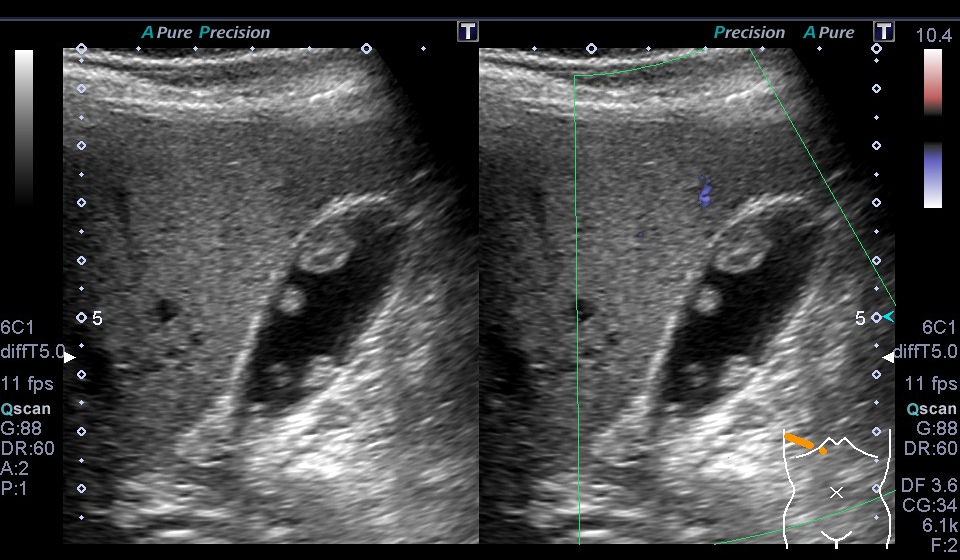

超音波(エコー) 診断画像

- 内頸動脈狭窄

- 膀胱がん

- 粉瘤

- 膝窩靭帯炎

- 乳腺症

- 乳がん

- 転移性肝がん

- 胆嚢ポリープ

- 胆石

- 大腸がん

- 前立腺肥大・前立腺がん

- 静脈瘤

- 腎細胞がん

- 子宮筋腫

- 心エコー(大動脈弁・僧帽弁閉鎖不全症)

- 鎖骨上転移

- 頸部リンパ節転移

- 胃がん

- バセドウ病